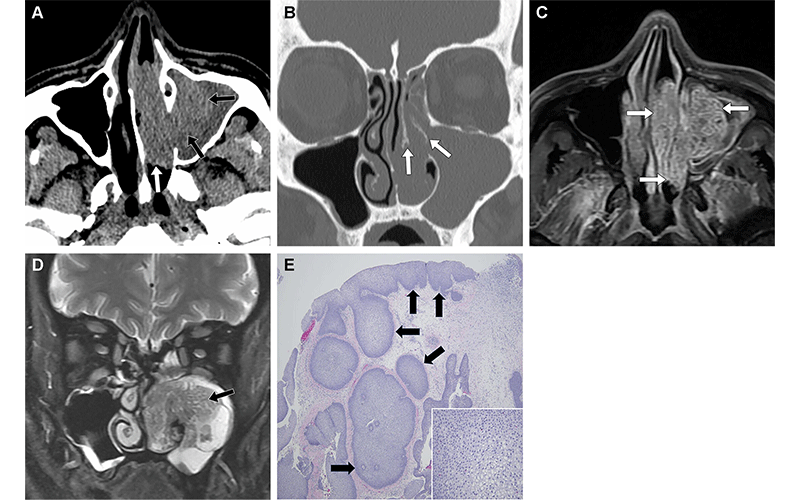

Inverted papilloma in a 66-year-old man who presented with a concern for sinusitis. (A) Axial soft-tissue unenhanced CT image shows a hyperattenuating mass in the left maxillary sinus (black arrows) with extension into the left nasal cavity (white arrow). (B) Coronal unenhanced CT image (bone window) shows hyperostosis of the left middle turbinate (arrows), likely reflecting the osseous attachment of this lesion. (C) Axial contrast-enhanced T1-weighted MR image shows that the mass enhances (arrows) after administration of contrast material, suggesting that this is not an antrochoanal polyp. (D) Coronal T2-weighted MR image shows that the mass has a “cerebriform” appearance (arrow), which is characteristic of an inverted papilloma. This mass was surgically resected. (E) Photomicrograph shows an inverted papillary growth pattern (arrows) with an otherwise flat apical surface. (Hematoxylin-eosin [H-E) stain; objective magnification, ×4.) Inset photomicrograph shows stromal edema with scattered infiltrating neutrophils, which are commonly observed. (H-E stain; objective magnification, ×40.) https://doi.org/10.1148/rg.240035 © RSNA 2024